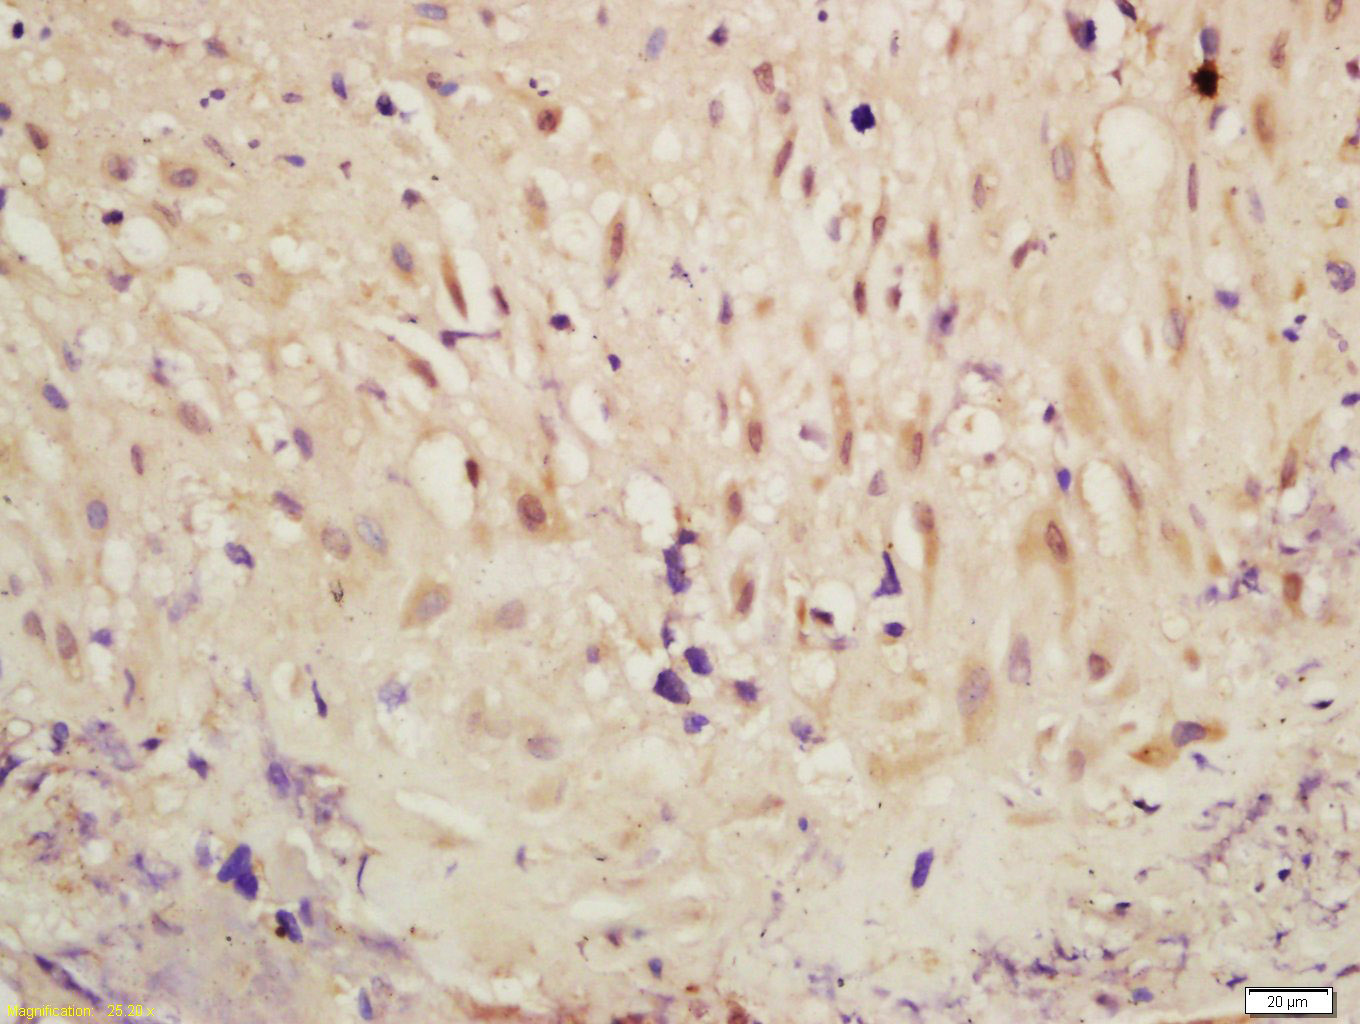

Antigen retrieval: citrate buffer ( 0.01M, pH 6.0 ), Boiling bathing for 15min; Block endogenous peroxidase by 3% Hydrogen peroxide for 30min; Blocking buffer (normal goat serum,C-0005) at 37℃ for 20 min;

Incubation: Anti-Phospho-RSK2(Ser227) Polyclonal Antibody, Unconjugated(bs-3367R) 1:200, overnight at 4°C, followed by conjugation to the secondary antibody(SP-0023) and DAB(C-0010) staining

Incubation: Anti-Phospho-RSK2 (Ser227) Polyclonal Antibody, Unconjugated(bs-3367R) 1:200, overnight at 4°C, followed by conjugation to the secondary antibody(SP-0023) and DAB(C-0010) staining